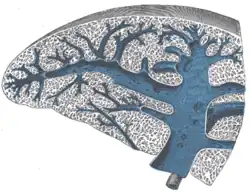

Secção transversa do baço, mostrando seu tecido trabecular, a veia esplênica e suas tributárias. -

Secção transversa do baço, mostrando a distribuição da artéria esplênica e seus ramos. -

Secção do baço, mostrando a terminação dos pequenos vasos sanguíneos. -